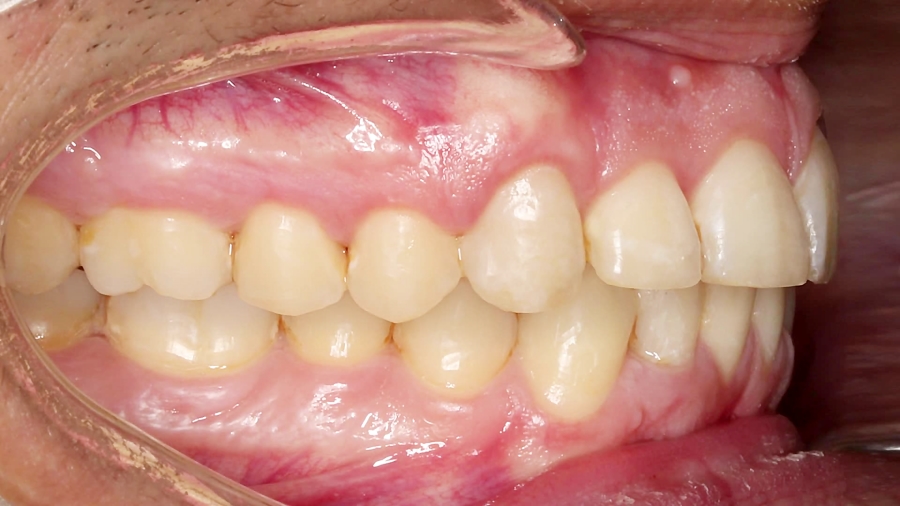

ارتودنسی، کامپوزیت و ایمپلنت | دکتر داودیان

474 بازدید